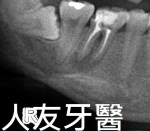

治療前

患者先前有矯正過一次,因為缺牙區縫隙很大,經醫師評估溝通療程為:植牙前先上矯正器,期間植入人工牙根等待植體與骨頭結合密度夠,矯正空間也足夠後開始取模型完成牙套裝置,拆除矯正器後利用居家美白療程來美白牙齒,完成後再裝置相同色階的牙套,顏色美觀又自然。